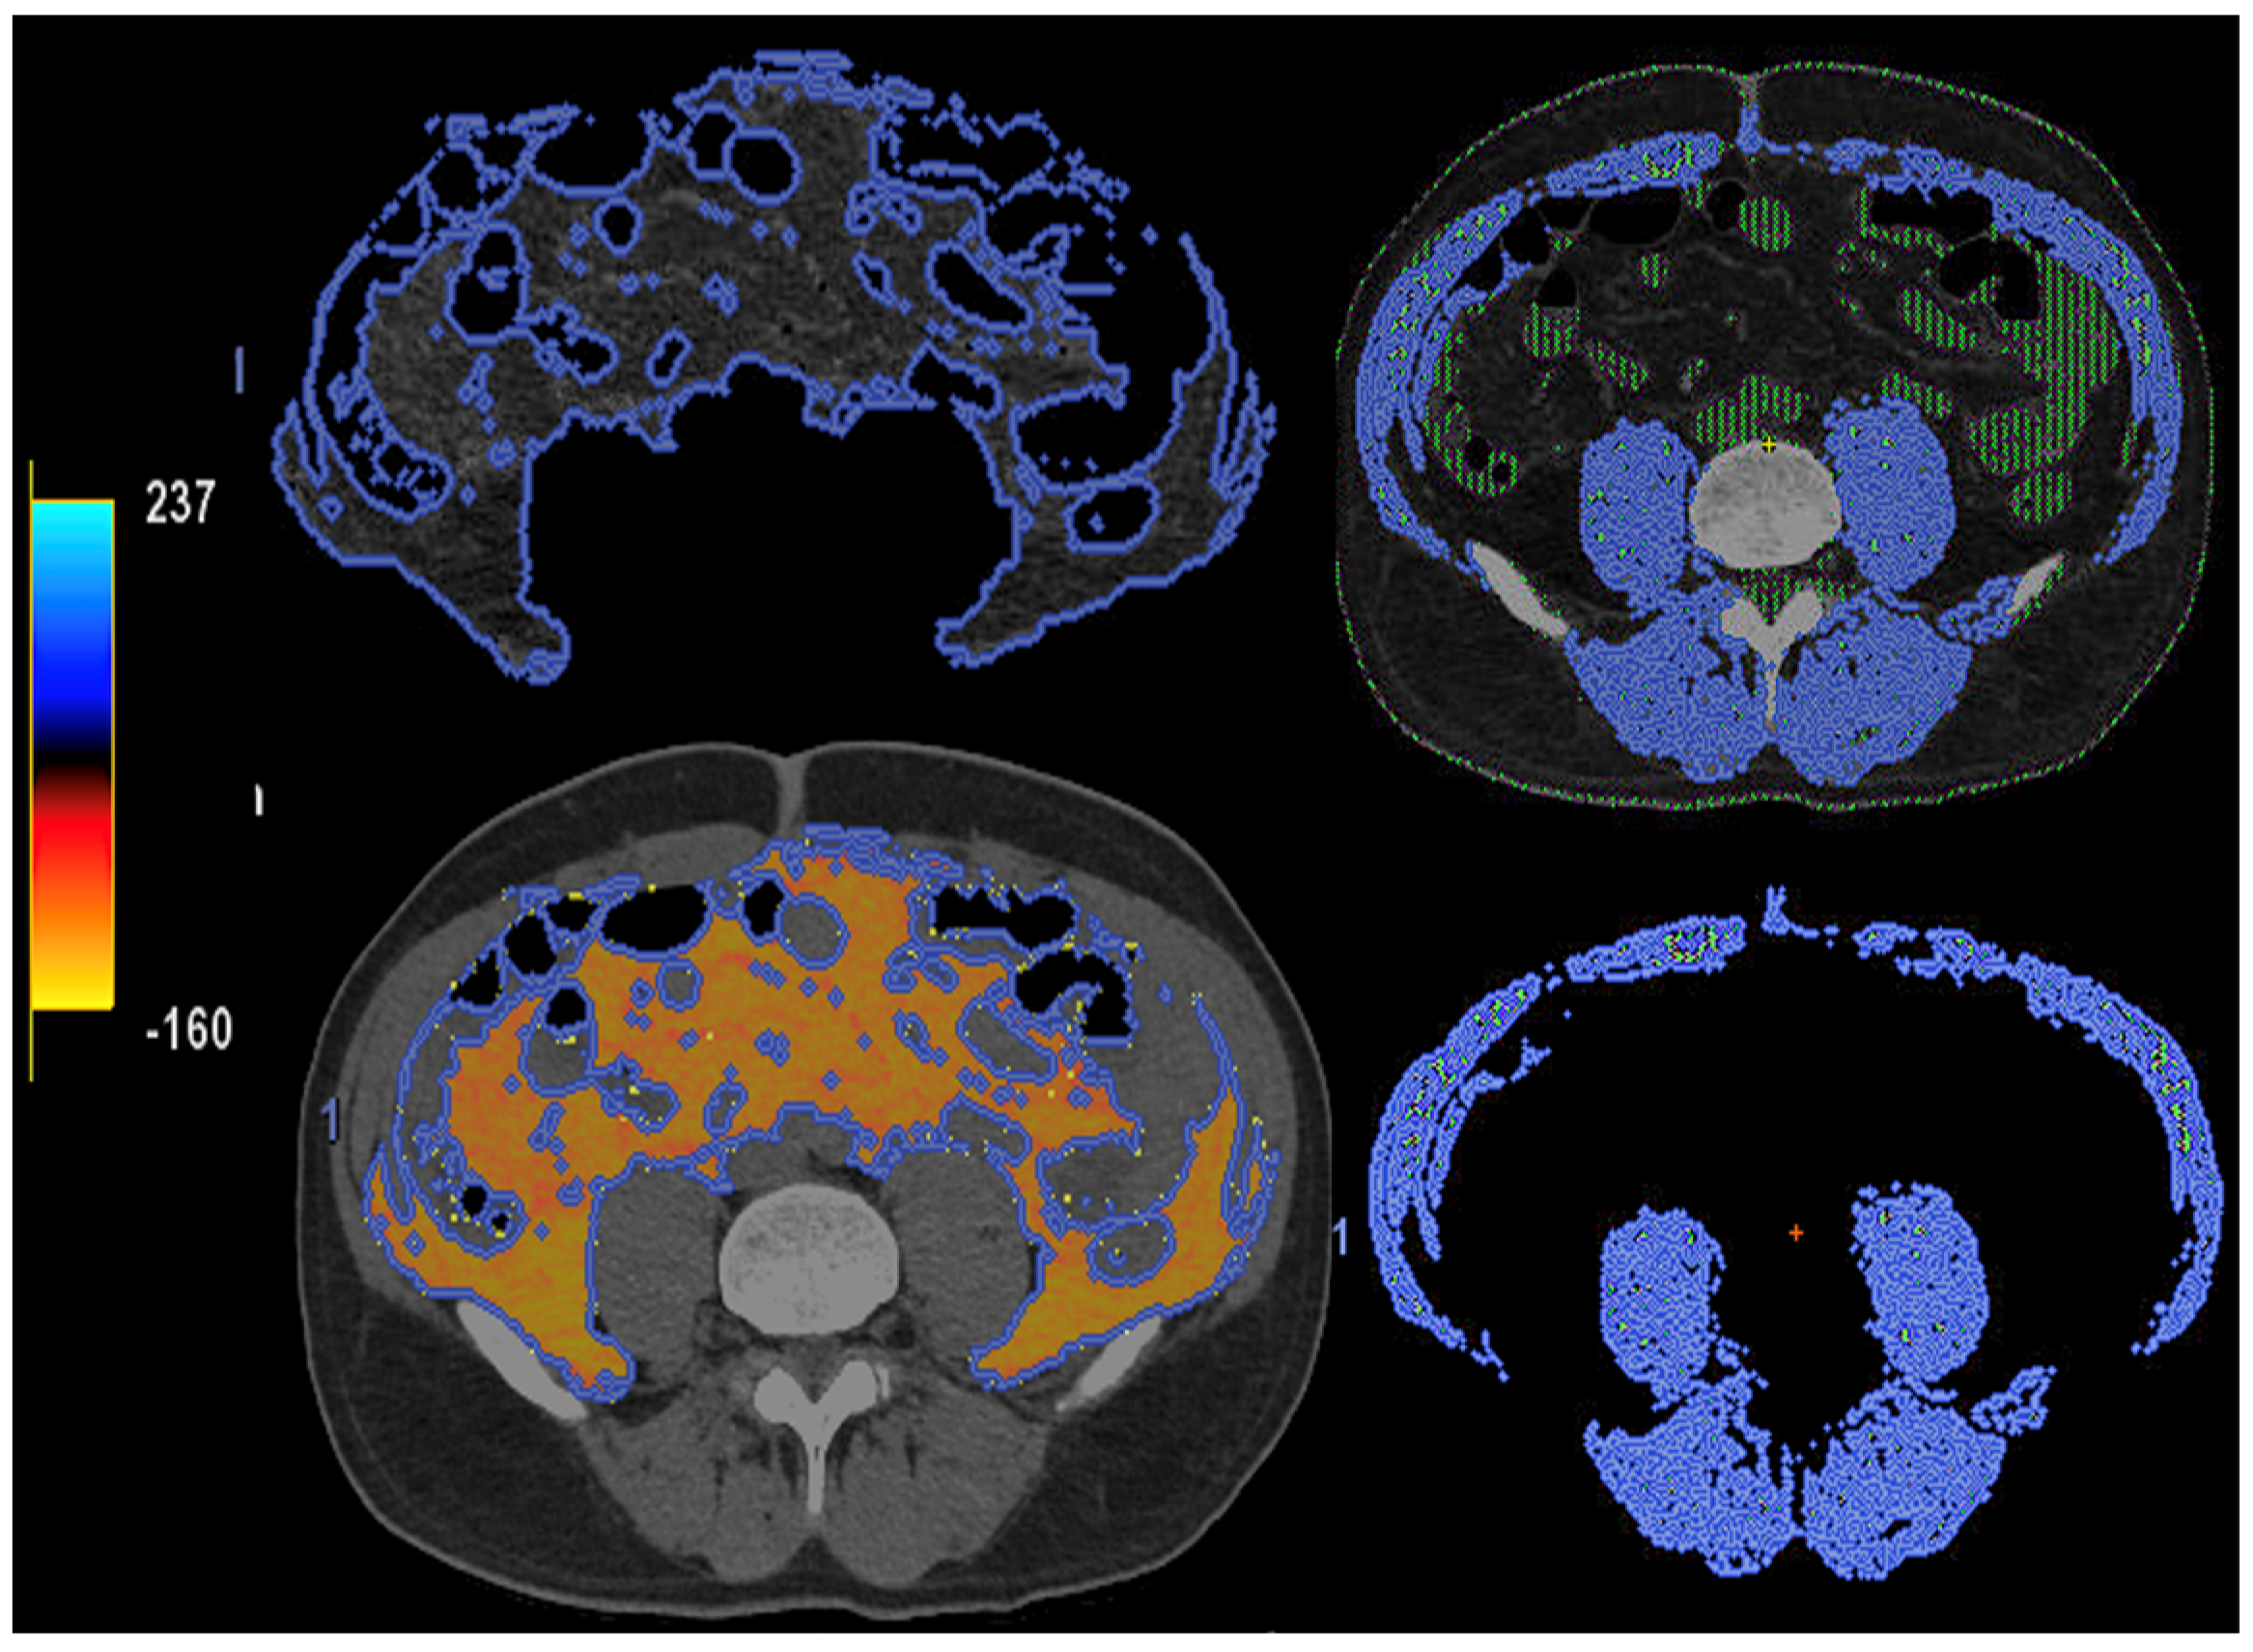

- Imaging of body composition is another growing application of DECT imaging that can be used to improve the evaluation of muscle tissue, visceral adipose tissue (VAT), and subcutaneous adipose tissue (SAT) compartments. SAT and VAT assessment is of special interest in diseases related to metabolic syndrome and critically ill patients [46]. Moreover, sarcopenia is associated with a poorer prognosis in cancer patients [47]. Measuring fat fraction of the skeletal muscle by DECT is a new approach for the determination of muscle quality, an important parameter for the diagnostic confirmation of sarcopenia [48]. In the case of bone mineral density analysis, DECT can provide a more detailed analysis when compared with dual X-ray absorptiometry [49] (Figure 15). Finally, DECT can also be a useful tool for evaluating silicone implants (Figure 16). Silicone contains the heavier element silicon (Z value = 14), whereas soft tissue predominantly comprises lighter elements, depicting the presence of silicone within the soft tissues in cases of silicone gel breast implant rupture and LN silicone spread [50].